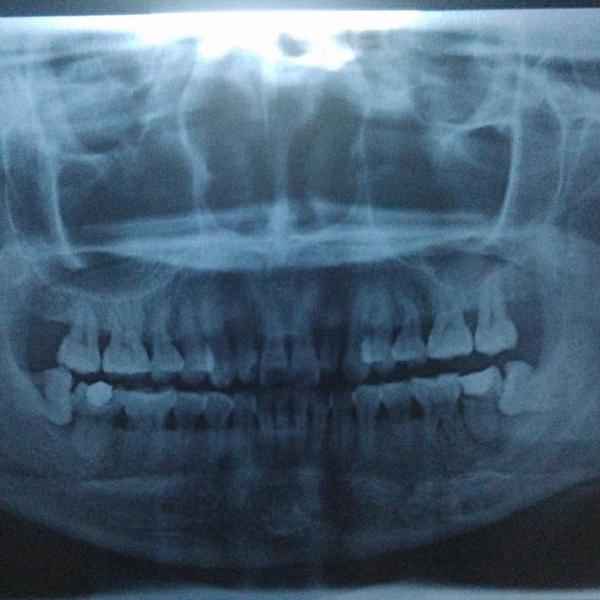

牙齿萌出困难称为 阻生齿 或 埋伏牙 。阻生齿最常见于下颌第三磨牙,俗称智齿,此牙萌出年龄在18岁前后,由于萌出前其它牙齿都早已站好队列了,等智齿生长出来时,就会受到其它牙齿的排挤,故而萌出困难,形成了阻生齿或埋伏牙,我们称之为 阻生智齿 。

大部分的智齿都应拔除。能早拔就早拔,拔晚了就会引起上述的危害。如果在妇女妊娠期发病会严重影响母子健康。20岁左右的年轻人正是在外地或外国上学的时期,如发生急性炎症,其家长往往会心急如焚,因此建议早早拔出阻生智齿,消除智齿的危害。

这种情况下就一定要先消炎然后拔除。否则以后你每次发烧感冒都可能使智齿感染,反过来也一样。 一般来说阻生智齿拔除不是大手术,上牙比下牙好拔除,但依据你的牙齿状况,过程可能持续10到15分钟,一定会打麻药,麻药负责你那半边脸的痛感缺失。手术过程中首先要划开牙龈,然后非常可能用到锤子和其他工具把牙撬出,或如果你的牙形比较细长,可能直接敲碎拿镊子夹出。手术风险:如果你的牙根非常长,长到和其下的神经有粘连,可能导致局部的永久性麻痹。术后:每个医生都会告诉你多久拿掉填充物多久可以刷牙。